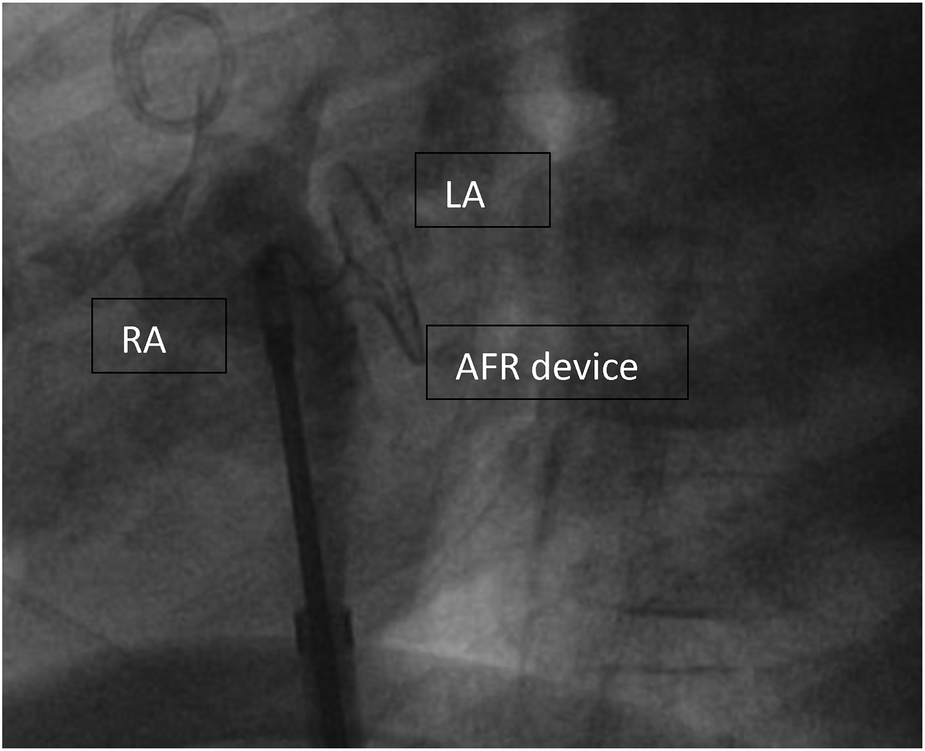

Due to the severity of the condition and the novel device, which was not CE approved then, we obtained informed consent, and the Ethical committee approved the off-label use of an 8ā mm AFR device. We performed the cardiac catheterisation under sedation. During induction, the child developed a PH crisis, which could be treated with Catecholamines and intravenous Prostacyclin. However, the second episode of a PH crisis occurred during device implantation. This time required a short period of resuscitation. Under the application of Adrenalin i.v. and Prostacyclin directly into the pulmonary artery, a stabilisation of the condition could be established. We perforated the intra-atrial septum with a Brockenorough transseptal puncture needle under the guidance of transesophageal echocardiography (TEE), the puncture hole was dilated, and a 12 Fr sheath was inserted over the interatrial communication into the left atrium so that 8ā mm AFR device could be deployed (FigureĀ 2). After confirming the correct position and checking the oxygen saturation level of greater than 85% and stable hemodynamic parameters, the device was completely and successfully released. The postinterventional echocardiography confirmed a right-to-left colour flow through the 8ā mm atrial communication (FigureĀ 3). After the intervention, anticoagulation with ASS was established.

Figure 2

Implanted AFR device (Occlutech, Germany) before disconnecting. AFR device (Occlutech, Germany) right before deployment, RA, right atrium; LA, left atrium.